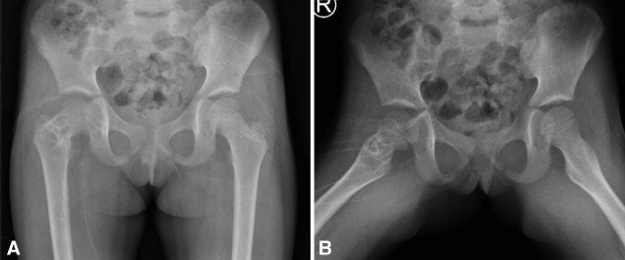

手术技术:经股骨近端外侧入路,逐层分离直至显露骨质。在转子区前侧皮质上使用钻头开窗,保留外侧皮质以用于固定,随后对病灶进行刮除,远端显露股骨髓腔,并取样送病理活检。其后,自外侧皮质向股骨头方向钻入 3 枚直径为 2 mm 的克氏针,至软骨下骨约 5 mm 。随后将克氏针弯曲成较大的弧形,以防止回弹及内翻移位,并加用一根环扎钢丝穿过股骨,以帮助增强稳定性(图 3)。最后,在病灶区域填充异体骨移植材料。切口关闭后,考虑到患儿年龄,予以半髋人字石膏固定 6 周(图 4)。若患者年龄更大且配合度更好,则可不使用石膏固定(见第二个病例)。术后 3 个月,拆除人字石膏并复查影像学检查(图 5)。

随访观察:随访期间发现,因患儿生长发育导致克氏针逐渐向股骨颈远端移位,使愈合周期延长——这恰是选用光滑克氏针而非螺钉的优势所在。图6展示了术后1年的影像资料。术后两年半,骨愈合完全,患者返院取出内固定物(图7)。内固定去除后1年随访显示(图8),股骨颈重塑至正常颈干角,末次随访时患者关节无僵硬、活动度无受限、无疼痛及跛行。